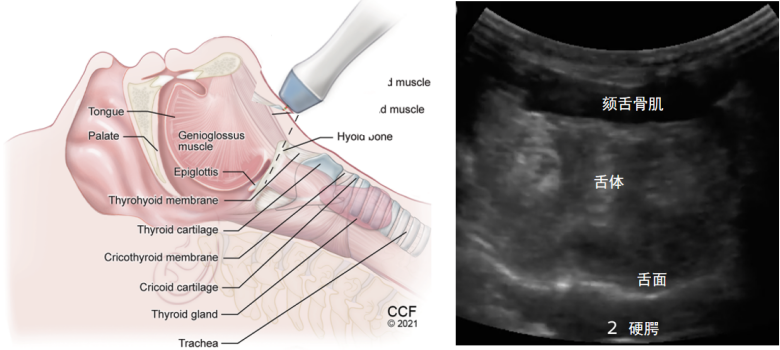

在矢状面,探头的标记点一般要求指向头侧,所以标记点指向下颏的位置,然后将探头置于下颏和舌骨之间,图4左为示意图,图4右为实际图像,从超声图像中我们可以依次看到舌骨肌、颏舌骨肌、舌下脂肪、颏舌肌,以及深侧的两条高亮的线(一条是舌面,一条是硬腭)。在矢状面可以测量舌体的厚度,以及下颏到舌骨的距离。

图片

图4  舌骨上切面:矢状面

将探头逆时针旋转90°,标记点指向患者右侧,即为舌骨上切面的横切面,由浅到深依次可以看到颏舌骨肌、舌体、舌面和硬腭(图5)。在横切面可以测量舌体的宽度。

图5  舌骨上切面:横切面